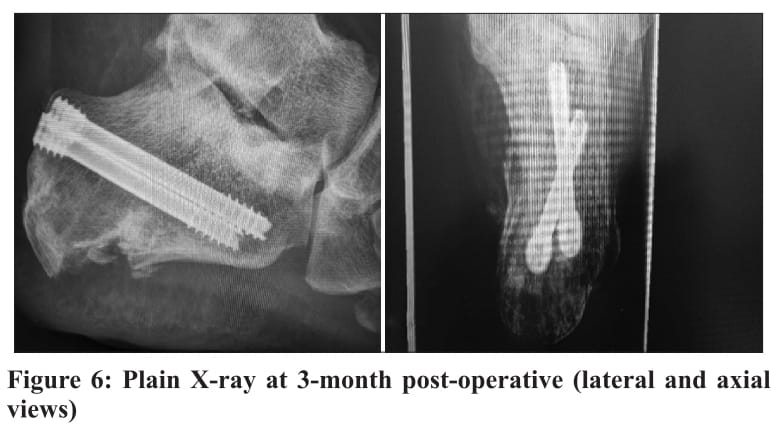

During the initial 2 weeks, the patient was wrapped in an elastic bandage and advised to engage in a gentle range of motion exercises for the ankle and subtalar joints. At the 2-week follow-up, with the wound fully healed, stitches were removed (Fig. 5). At 6 weeks, partial weight-bearing at 20 kg was initiated, utilizing an air cast walker, and a gradual progression to full weight-bearing was achieved by 10 weeks. X-rays were performed at 1-week, 6-week, 3-month, and 6-month postoperatively, (Fig. 6).